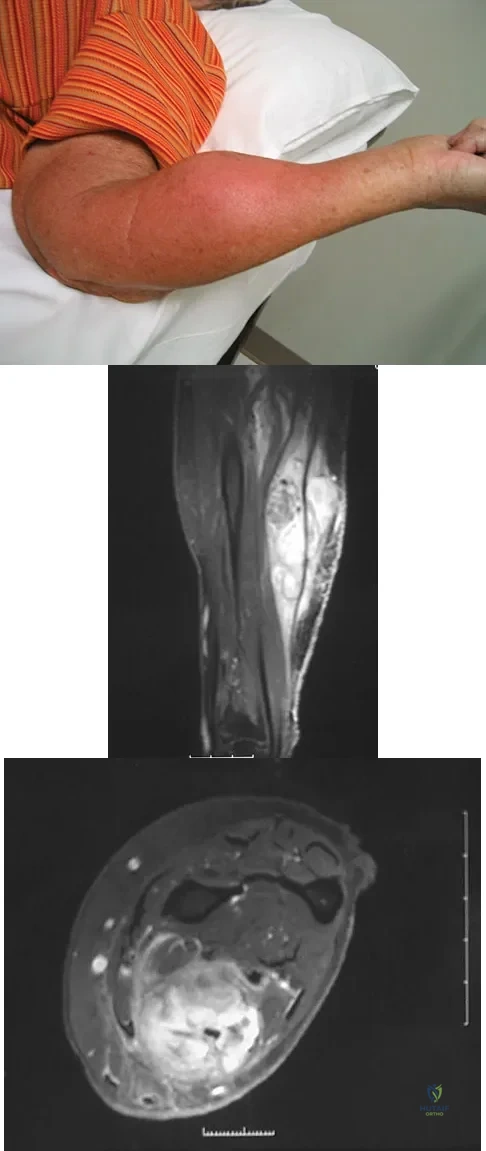

Figure 8a shows the clinical photograph of an 83-year-old woman who has an enlarging left forearm mass. MRI scans are shown in Figures 8b and 8c. What is the next most appropriate step in management?

Explanation